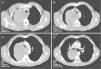

In the computed tomography images, one can observe in the middle mediastinum a large mass measuring 12×9.7cm that is heterogeneous, with well-defined edges and hypodense areas in its interior (A). The lesion compresses the trachea and displaces it towards the left (B and C) and it extends up to the entrance of the right upper bronchus, displacing it and compressing the end of the bronchus and the parenchyma of the upper right lobe (D).

The patient is a 50-year-old male, a smoker, who in 2004 had been diagnosed with DFSP that was 7cm in diameter and located in the left scapulohumeral region. The initial treatment was surgical, but after the resection the deep edges were affected. The patient had several local relapses that were treated surgically in 2006 and 2009. In the last surgical biopsy, the edges were tumor-free and the patient received no adjuvant treatment. Recently, the patient came for a consultation due to fever, arthralgia and unproductive cough. Radiography showed a paratracheal mass. CT confirmed the presence of a heterogeneous mediastinal mass with compression of the adjacent structures (Fig. 1). Bronchoscopy revealed edematous mucosa at the entrance of the main bronchus and the upper right lobe. Blind TBNA was performed with an MW-319 histology needle (Bard-Wang, Billerica, MA, USA) and the anatomopathologic result was DFSP metastasis, based on the morphology of the biopsies and supported by immunohistochemistry techniques (strong expression of vimentin and CD34) and by the genetic-molecular study (presence of translocation of chromosomes 17 and 22).